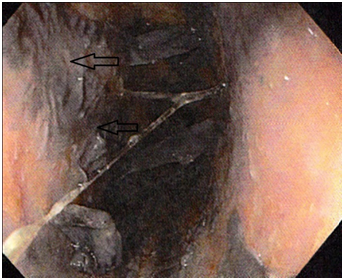

A 79year old chronic smoker (60 pack years and ex-smoker for 30years) male with no significant medical history was admitted for painless, persistent, progressive odynophagia for two weeks. He reported loss of appetite, change in voice, and unintentional loss of 40 pounds with loss of taste in two months associated with constipation. He denies nausea, vomiting, abdominal pain, lower abdominal discomfort, chest pain, cough, palpitation, hematemesis, hemoptysis or melena. Physical examination was unremarkable except mild tenderness in left lower quadrant, no guarding or rigidity, bowel sounds heard in all four quadrants but no palpable organomegaly. Basic metabolic panel and Liver function test are within normal limit. CEA was 1162 and CA 19.9 was 5885.3. Abdomen X-ray showed moderate amount of stool in the colon and chest X-ray showed bilateral rounded opacities of uncertain etiology. Due to anemia work up and negative fecal occult blood, CT scan of abdomen with contrast was done and showed neoplasm of distal sigmoid colon and rectum with extension along inferior mesenteric artery, para-aortic, retroperitoneal, and pelvic lymphadenopathy, metastatic disease to the liver, lungs and bones, and thrombosis of the right portal vein. Later, EGD showed LA class D esophagitis seen at 25cm from incisor extending up to 40cm. Overlying blackish exudate was seen at area of the esophagitis (Figure 1). Colonoscopy showed large, erythematous, near obstructing friable mass at the recto-sigmoid junction. Multiple biopsies were taken from the mass. In order to relieve lumen obstruction, metallic colonic stent was placed .Pathological report from Esophagus showed squamous esophageal mucosa with mild acute nonspecific esophagitis (Figure 2) (Figure 3) but no fungus detected by PAS stain. Antrum and body biopsy report showed mild chronic nonspecific gastritis. Recto-sigmoidal biopsy showed Infiltrating adenocarcinoma (Figure 4). Surgery team was consulted but the patient is not a candidate for surgical procedure. Oncology was consulted for aggressive treatment but the patient and family appreciated palliative care and he is on enoxaparin for portal vein thrombosis.

Figure 1 Endoscopic view of the middle esophagus revealing black mucosa with friable tissue.